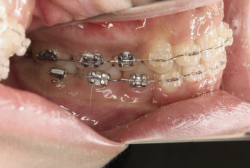

「乳歯が生え替わらない」という主訴で来院したケースです。 診断の結果、「左上永久犬歯が第一小臼歯後方上部に埋伏しているため、左上乳犬歯が晩期残存している症例」と判明しました。

このような症状の場合は、手術で埋伏している永久歯に金具を取り付け、矯正装置で牽引する必要があります。同時に凸凹の解消と前突した前歯を内側に入れるために上下左右の小臼歯を抜歯させて頂くことといたしました。

この方の場合は、マルチブラケット装置にて治療を開始し、治療期間2年3ヶ月で終了しました。犬歯の牽引距離が非常に大きかったため当院の平均治療期間よりも大幅に期間がかかりましたが、埋伏犬歯を完全に正しい位置まで誘導することができました。同時に 前歯の前突と配列の凸凹も解消しました。

マルチブラケット装置は、装置装着時より数日から2週間程度強い不快感疼痛が有りますが、本症例場合は埋伏歯を開窓手術し、遠く離れた位置に矯正器具が付いていますので強い違和感が生じ、歯ブラシも届きにくく口腔衛生状態を保つのにはかなりの努力が必要です。条件の悪い場所に接着されているため、装置が外れやすく日常生活上もかなり配慮が必要となります。

また、埋伏歯は移動距離が大きくなることが多く、歯根吸収のリスクが高まりますので、移動と休止にゆとりのある治療間隔が必要です。